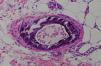

A skin biopsy of the affected area revealed superficial ulceration with necrosis of the superficial dermal collagen, as well as extensive calcification and intimal proliferation in multiple arteries and arterioles (Fig. 2). The calcium deposits in the blood vessel walls were more visible with Von Kossa staining. As there were no extravascular calcium deposits or fat necrosis, the diagnosis of calciphylaxis was confirmed. Because the patient had normal levels of protein C, protein S, parathyroid hormone, calcium, and serum phosphate, a diagnosis of atypical calciphylaxis was established.